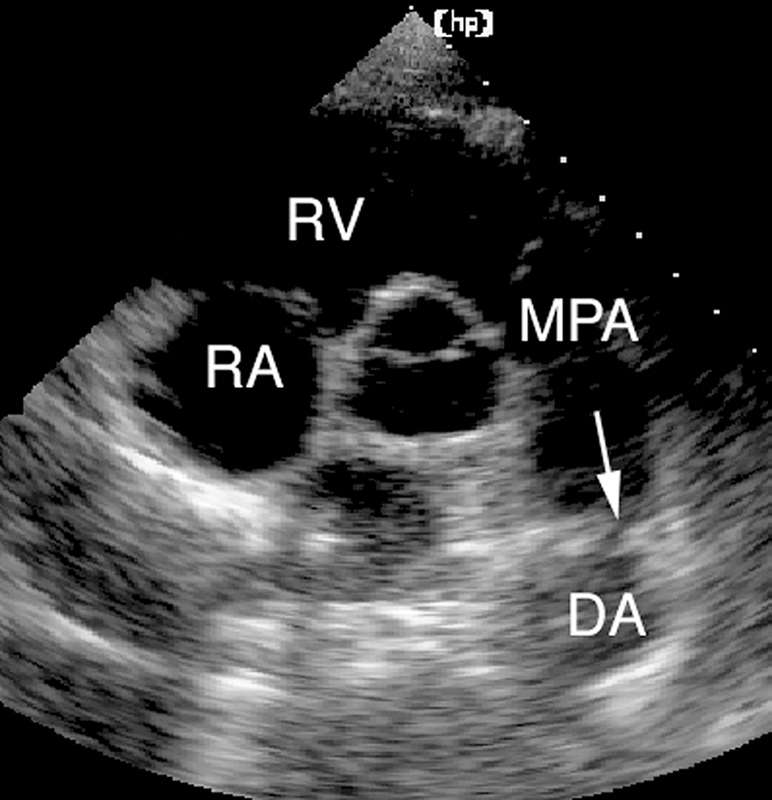

فحوصات تشخيصية لبعض امراض القلب والشرايين التاجية